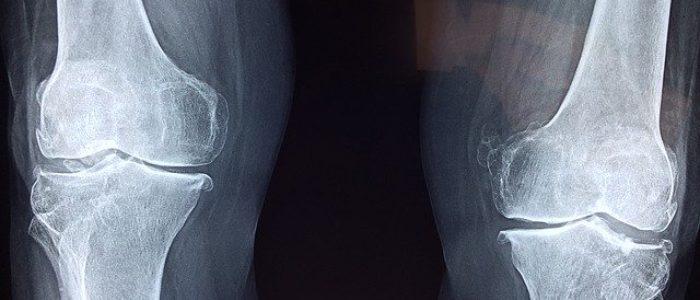

מי שנפצע במהלך העבודה, בין אם פציעה חמורה (כמו נפילה מגובה שהובילה לשברים או לנכות) לבין אם מדובר בפגיעה שנוצרה במהלך השנים (כמו למשל עיוורון עקב חשיפה לחומרים כימיים), כדאי שיבדוק את הזכויות שלו בביטוח לאומי.